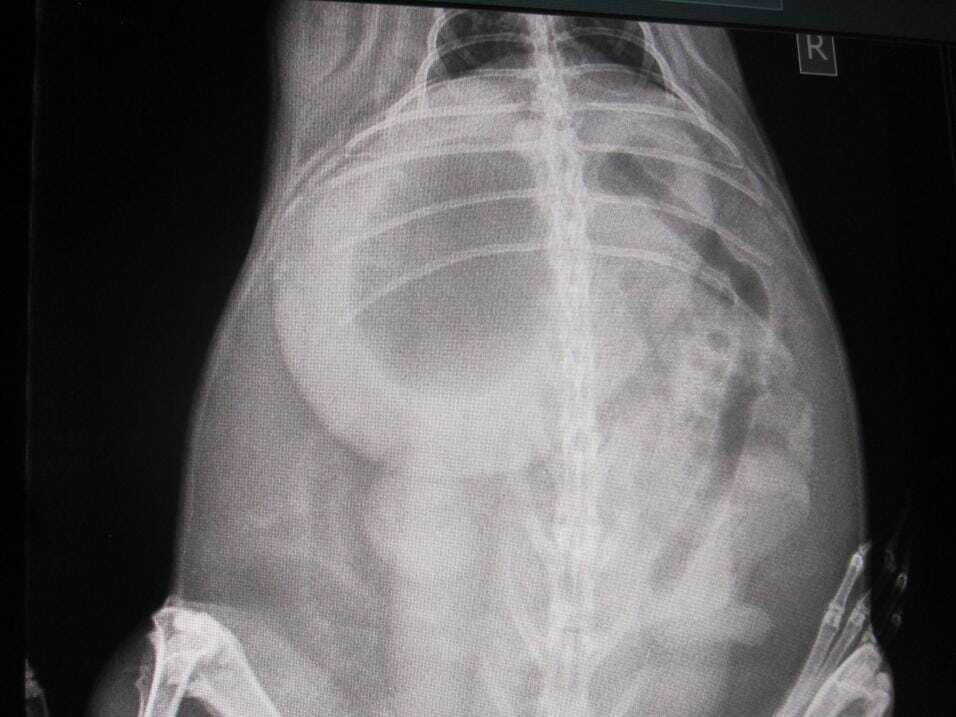

Where an obstruction is suspected, it is useful to check a blood glucose level. Rabbits that have very high blood glucose when in gut stasis are more likely to have a gut obstruction, although this is not diagnostic. If the blood glucose is high, then X-rays (Figures 1 to 3) or ultrasound should be used to further rule in or out an obstruction.